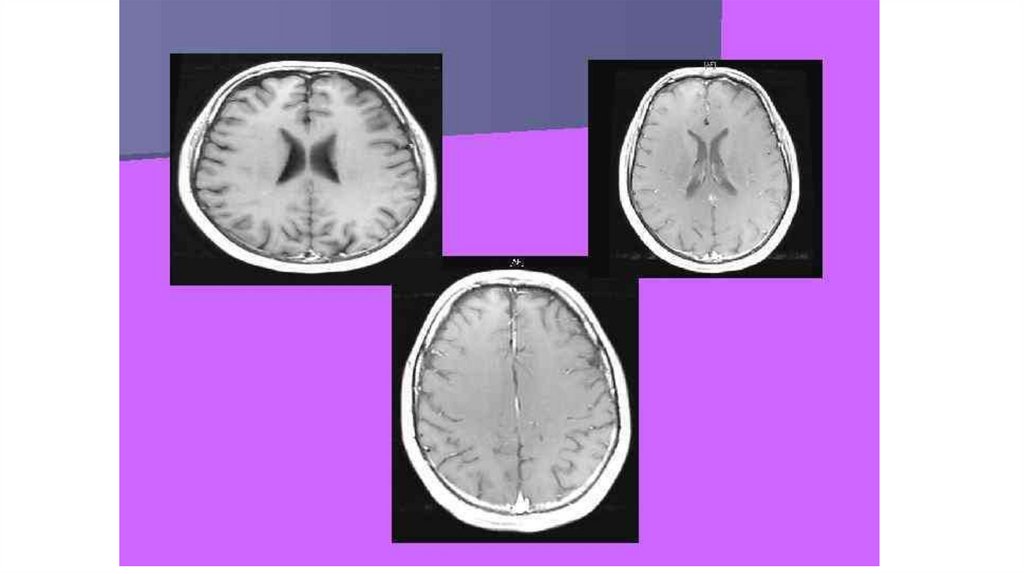

Анатомічна будова великих півкуль

Будова :

1.Півкулі

-Права півкуля

-Ліва півкуля

2..Мозолисте тіло ( перетинка )

3.Звивини ( у вигляді гребенів )

4.Борозни ( у вигляді заглибин )

Мікроскопічна будова ВЕЛИКИХ ПІВКУЛЬ

1.сіра речовина

-кора

Будова кори

1.товщина 3-5мм

2. 6 шарів нейронів ( в кожному шарі певний вид нейронів)

3.площа 1400- 1600 см2 ( площа набагато більша чим площа мозку , але

кора знаходить та охоплює також борозни , заглибини що є у мозку )